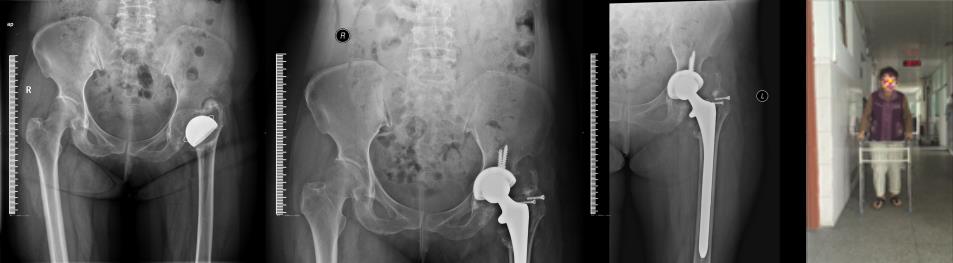

刘*,女,57岁,30年前因外伤致左股骨头骨折而行半髋置换术治疗。入院前因疼痛伴跛行2个月就诊,多家医院不敢手术,在我科手术后一周即下地活动。